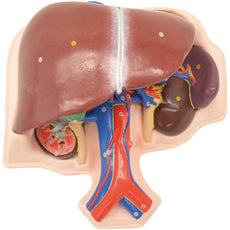

This Urinary System all-in-one-model shows:- Structures of retroperitoneal cavity

- Large and small pelvis with bones and muscles

- Inferior vena cava

- Aorta with its branches including iliacal vessels

- Upper urinary tract

- Rectum

- Kidney with adrenal gland.

One front half of a kidney is removable from the anatomical model of the urinary system. With easy to change male insert (bladder and prostate, front and rear half) and female insert (bladder, womb and ovaries, 2 lateral halves) the Urinary System model is a great teaching tool.

Dual Sex Urinary System model on baseboard.